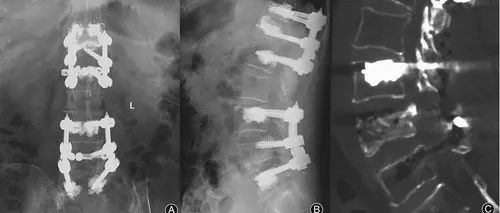

合并帕金森病的Kummell病内固定失败病例报道

Edited by Spine Truth Editorial Team脊柱甘露语林®学术•疾病与健康科普•助学•公益行之2514天,第1554篇Kummell 病于1891年首次被描述,患者在脊柱轻微外伤数周至数月没有任何症状,但随后逐渐出现背痛、椎管狭窄、神经功能缺损、脊柱不稳、进行性后凸畸形等症状,可以认为是发生在椎体上的骨不连。Kummell 病保守治疗通常无效,后期可能出现神经损害或严重的脊柱后凸畸形等问题。由于外科治疗效果可靠,手术治疗得到了许多学者的高度评价。...